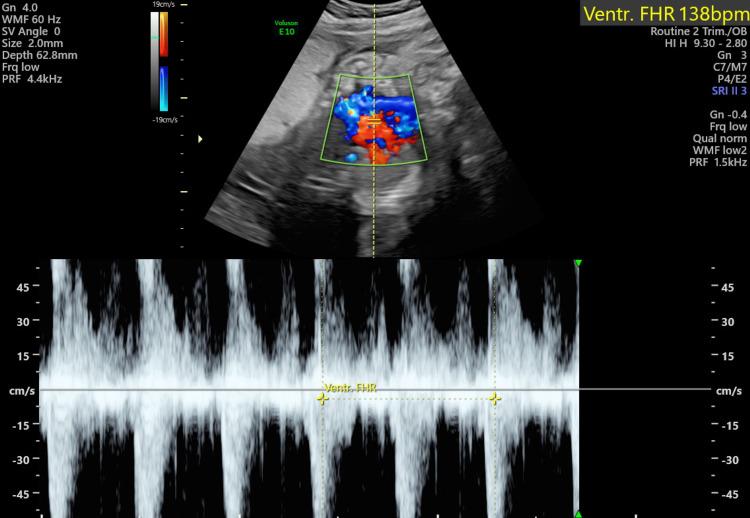

Chorioangioma is a benign placental neoplasm seen in about one percent of all pregnancies. The larger neoplasms generally cause severe foeto-maternal complications. We are reporting a case of a 33-year-old gravida three para two female who was incidentally diagnosed with chorioangioma at her routine 28-week antenatal follow-up. She delivered a preterm small-for-gestational-age female baby at 34 weeks with complications. Therefore, an early diagnosis warrants a close follow-up and timely intervention for a better outcome of the pregnancy.

绒毛膜血管瘤是一种良性胎盘肿瘤,在所有妊娠中约占1%。较大的肿瘤通常会导致严重的母婴并发症。我们报告一例33岁、孕3产2的女性病例,她在28周常规产前检查时被意外诊断为绒毛膜血管瘤。她在34周时早产了一名小于胎龄的女婴,并伴有并发症。因此,早期诊断需要密切随访并及时干预,以获得更好的妊娠结局。